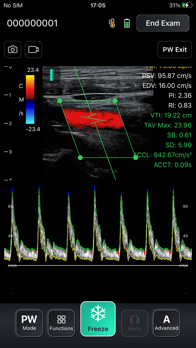

The ASUS MediConnect app is designed for handheld ultrasound solutions, delivering high-quality imagery and enabling swift patient diagnosis

It has an intuitive UI designed for both portable devices and computers, allowing the user to view ultrasound scans in real-time

Annotations and medical measurements can also be done via the MediConnect app in real time.